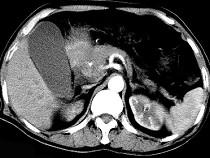

问题 男50岁黄疸进行性加重、腹部胀痛不适、食欲减退、体重减轻、上腹部可触及肿块,CT如图,最可能的诊断为 ( )

选项 A.急性胰腺炎 B.慢性胰腺炎 C.胰头癌 D.腹膜后淋巴瘤 E.转移瘤

答案 C